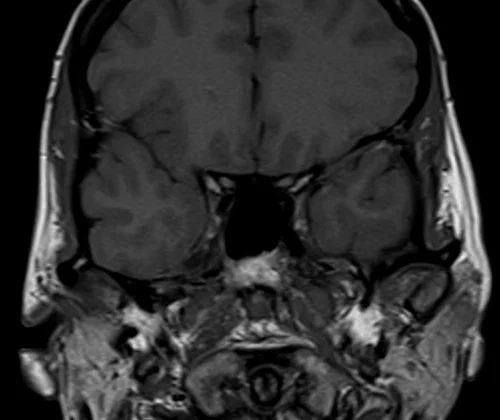

Brain epilipsy protocol mri coronal T1 images